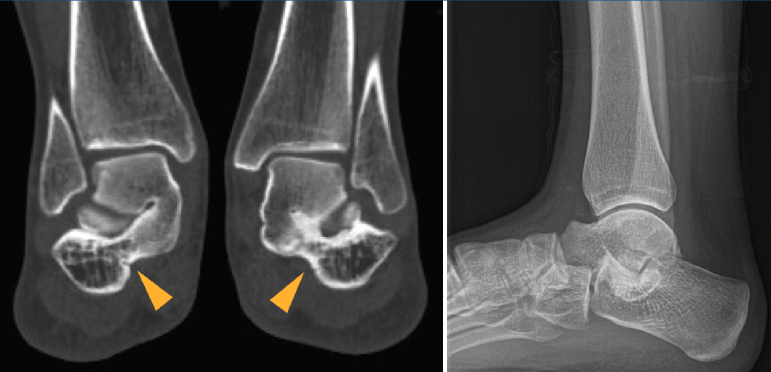

Figura 1. Segundo caso: coalición tarsal talocalcánea sinostótica bilateral. Pie derecho. Tomografía axial computarizada y radiografía.

Se trata de una paciente mujer de 18 años de edad, higienista dental, sin antecedentes patológicos de interés, que presenta pies planos valgos bilaterales dolorosos, el derecho de 23° y el izquierdo de 21° de valgo, por sinostosis calcaneoastragalina media en ambos pies. En ella observamos básicamente una clínica de dolor en el seno del tarso, con déficit de movilidad de la articulación subtalar en ambos pies. Se realiza estudio mediante radiografías de los pies y los tobillos en carga y TAC de ambos pies (afectación bilateral). Radiológicamente, las articulaciones tibioperoneoastragalina y subtalar están preservadas. Se diagnostica de coalición tarsal de tipo 4 de la clasificación de Rozansky(26). El balance articular es de: flexión = 45°; extensión = 20°; inversión = 0°; eversión = 0°. La escala de la AOFAS para el tobillo derecho presentaba una puntuación de 62 (20-37-5). Los ángulos radiológicos iniciales son: Moreau-Costa-Bartani interno = 141°; declinación talar = 18,4°; Meary = 6,3°; Kite = 25,6°; taloescafoideo = 48,3°.